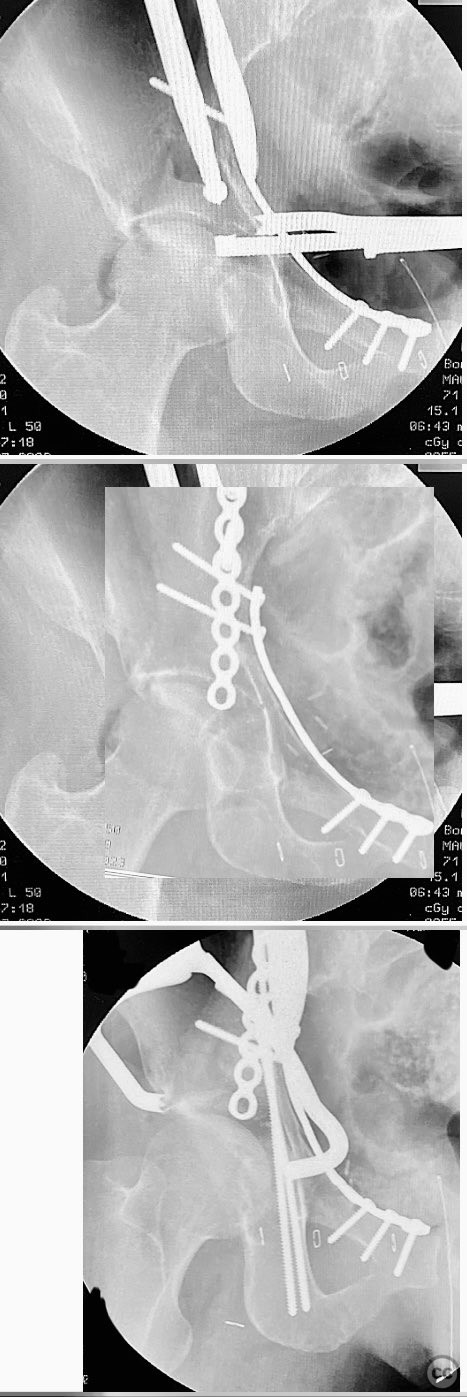

Anatomical surgical approach:  A classical ilioinguinal approach was utilized. The incision was made parallel to the inguinal ligament, extending from just lateral to the anterior superior iliac spine (ASIS) towards the pubic tubercle. Dissection proceeded through the subcutaneous tissue and external oblique aponeurosis, with careful identification and protection of the neurovascular structures within the three windows of the ilioinguinal approach. The anterior column fragments were exposed and reduced using clamps. The quadrilateral surface and posterior column were buttressed with a contoured reconstruction plate. The medial dome impaction zone was identified under fluoroscopic guidance, reduced to the femoral head, and supported with allograft bone. The anterior column reduction was stabilized with a contoured reconstruction plate, and additional lag screws were placed as needed to secure the posterior column.

Operative remarks:

Manual traction intraoperatively demonstrated the appropriate position of the femoral head. Reduction of the quadrilateral surface and posterior column was achieved prior to addressing the impaction zone. The impacted dome fragment was anatomically reduced and supported with allograft bone grafting. An offset clamp was utilized to improve posterior column reduction when necessary before definitive fixation with lag screws. Intraoperative fluoroscopy confirmed satisfactory reduction and implant placement.